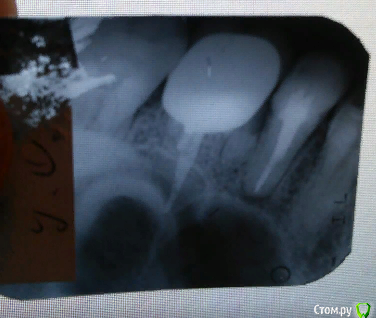

kryger2010 Опубликовано 10 сентября, 2019 Автор Поделиться Опубликовано 10 сентября, 2019 Вечером выложу рентген но он прицельный, есть панорамный снимок, но сделанный до установки коронки... Ссылка на комментарий

kryger2010 Опубликовано 10 сентября, 2019 Автор Поделиться Опубликовано 10 сентября, 2019 До установки и после Ссылка на комментарий

DmitrySH Опубликовано 11 сентября, 2019 Поделиться Опубликовано 11 сентября, 2019 Здравствуйте. По вашим снимкам сложно сказать что-то конкретное. Прицельный снимок сделан так, что прилегание коронки по нему невозможно оценить. Но видно у зуба 15 есть хроническое воспаление и пародонтальный карман. 2 Ссылка на комментарий

St. Опубликовано 11 сентября, 2019 Поделиться Опубликовано 11 сентября, 2019 Посмотрите пожалуйста присоединяюсь к ответу выше. Снимок с коронкой сделан слегка под углом и по нему не понятно как коронка соотносится с корнем. воспалена десна, а я ее еще и руками трогаю периодически и тем самым провоцирую "замкнутый круг" болит, ищу причину и трогаю и тем самым усугубляю все. вполне логичное обьяснение. В таком случае чистить как обычно(только щетку лучше все же средней жесткости), плюс мазать десну метрогилом, полоскать хлоргексидином 0,05%, и пока на неделю-другую оставить в покое.Понаблюдайте поменяется ли что-то. он появился из за нависающей пломбы,......карман как понимаю, полному устранению не подлежит. Да 1 Ссылка на комментарий